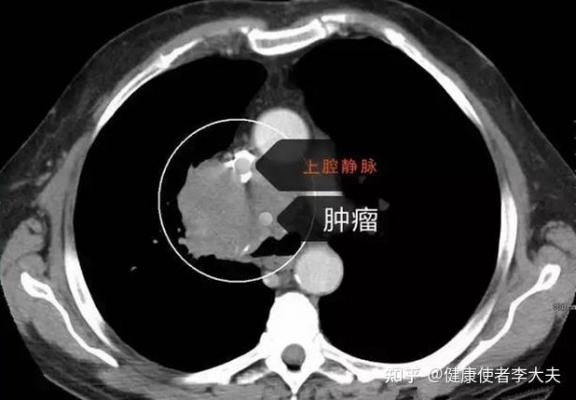

肺癌晚期還有救嗎?腫瘤醫生提醒你,6個癥狀很難熬肺癌作為中國癌癥的第一殺手,早期臨床癥狀并不明顯,一旦發展到了晚期,癌細胞就會不斷擴散。以下這6個十分煎熬的癥狀,于醫生今天帶...